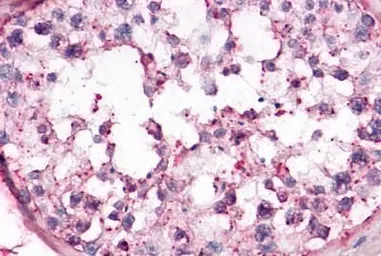

OR10R2 antibody

Cat. No. GTX71527

ApplicationsIHC-P

ReactivityHuman, Rabbit, Bovine, Monkey